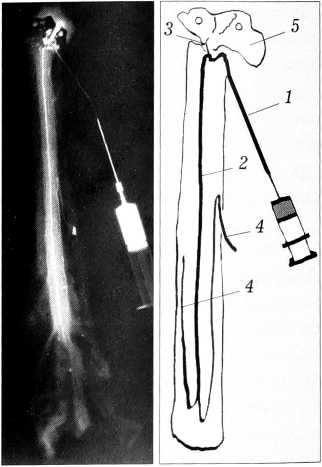

Во всех исследованных препаратах, в том числе и в полученных от погибших в результате ката- травмы, отмечено сохранение сосудистой системы передней спинальной артерии на всем протяжении. Исключение составил один случай ката- травмы с прямым механическим повреждением вещества спинного мозга, в котором было найдено повреждение передней спинальной артерии (рис. 3).

Рис. 3. Магистральный тип кровоснабжения спинного мозга, кататравма. 5 — разрыв восходящего отдела передней спинальной артерии (остальные обозначения те же, что на рис. 1).